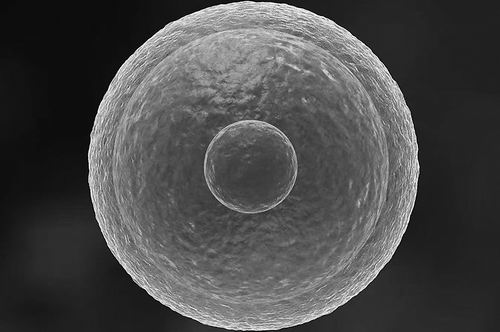

卵细胞。

然而,健康的人类卵细胞似乎避免了这个问题。为探究原因,B?觟ke团队在显微镜下观察了提取的人类卵细胞。他们将其置于含荧光染料的液体中,这种染料能标记细胞内的溶酶体,而后者是负责废物回收的“细胞回收站”。结果显示,人类卵细胞中的溶酶体活性显著低于其他人类细胞或小鼠等哺乳动物卵细胞的活性,表明其废物处理速度明显放缓。不同于其他细胞频繁“自我清洁”,卵细胞似乎选择了“少动为妙”的策略。